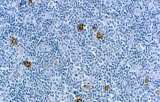

- Linfoma di Hodgkin classico: le cellule tumorali sono tipicamente CD30+ e spesso CD15+, con PAX5 debole e CD20 negativo nelle grandi cellule tumorali.